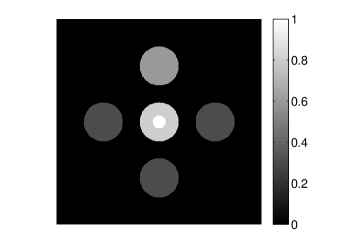

The numerical phantom shown in Figure 1(a) was employed. The phantom had a support area of mm2 and contained six uniform disks that were assigned different values of absorbed optical energy density.

A 2D circular measurement geometry was employed. transducers were evenly distributed on a ring of radius mm that enclosed the phantom. The SOS was assumed to be constant and set at mm/s. Since the simulated data were formed by use of the C-D imaging model in Eqn. (2), no inverse crime was committed. The components of this vector corresponded to equally spaced temporal samples over the interval s. Subsequently, the noiseless voltage vector was obtained by convolving the pressure data with EIR-1 in Figure 1(b).

The reconstruction region ( mm2) was represented by pixels with pixel size mm in each dimension. The initial guess of the EIR employed in the VP algorithm was different than the EIR that was assumed when generating the simulated data. This served to simulate a situation in which an experimentally measured EIR contained errors.

Each element in a real-world transducer array possesses its own EIR. In practice, the differences between the EIRs are sometimes neglected and an EIR corresponding to a single element may be used to represent all elements in the array. In some of the studies below, the EIR employed to initialize the VP algorithm (EIR-2 in Figure 1(b)) and the EIR employed to produce the simulated measurements (EIR-1 in Figure 1(b)) were experimentally measured from two different transducer elements in a circular transducer array (see Sec. VI-B). EIR-1 was measured by temporally integrating the PA signal produced by a point source positioned at the focus of the transducer. EIR-2 was measured by use of the method reported in [RNR2011]. In order to investigate the sensitivity of the VP algorithm to the initialization of the EIR, we employed different EIRs obtained by degrading EIR-1 as described later. When solving the sub-problem in Line-2 of Algorithm 1, was initialized as the zero vector. Algorithm 1 was terminated after 500 iterations, since it was observed that the changes in the reconstructed images with more iterations were negligible. When implemented by use of a single core of an Intel Xeon E5-2640 CPU, each iteration required approximately 7s to complete.